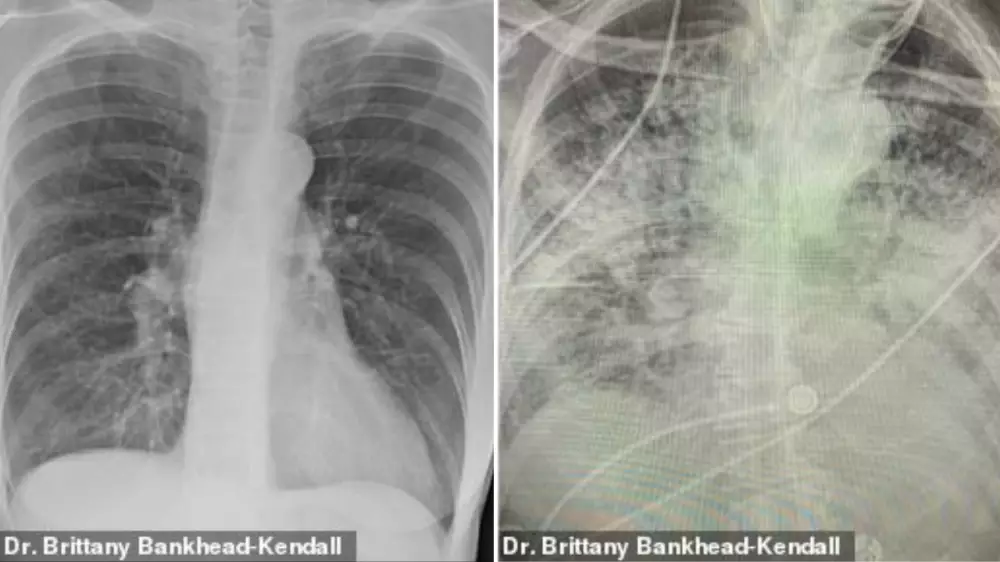

Доцент Центра медицинских наук Техасского технологического университета, доктор Бриттани Бэнкхед-Кендалл показала три рентгеновских снимка легких: здорового человека, курильщика и пациента с коронавирусом.

По словам хирурга, легкие выздоровевших пациентов с COVID-19 выглядят намного хуже, чем у курильщиков. Снимок выглядел почти полностью белым. Врач пояснила, что помутнение легких обычно указывает на то, что они наполнены такими веществами, как жидкость или бактерии, а также плотными рубцами и повреждениями.

У курильщика они частично побелели от рубцов, и снимок выглядит слегка туманным.

На рентгеновском снимке здорового пациента много черного пространства, что является показателем нормального количества кислорода.

"Легкие после коронавируса выглядят хуже, чем любые ужасные легкие курильщика, которые мы когда-либо видели. И они разрушаются", - заявила она.

По ее словам, многие эксперты в области здравоохранения концентрируют внимание на показателях смертности, а не на долгосрочных последствиях выживших. Доктор Бэнкхед-Кендалл также отметила, что почти у всех пациентов из тех, кого она лечила, и тех, кто переболел коронавирусом, был плохой рентген грудной клетки.

Врач добавила, что коронавирус часто приводит к таким осложнениям, как пневмония, которая возникает при наполнении легких жидкостью. Поскольку воздушные мешочки наполняются жидкостью, они не могут принимать достаточно кислорода и воспаляются, что приводит к таким симптомам, как кашель и одышка. Она подчеркнула, что если человек все еще испытывает одышку после выздоровления от COVID-19, то ему стоит немедленно обратиться к врачу первичной медицинской помощи.